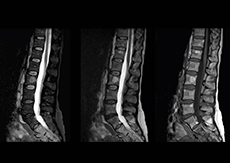

“In our lumbar spine MRI, the value of mDIXON TSE is so obvious. Normally we perform T1 and T2 scans in sagittal and transverse orientation.It used to take too much time to add a sagittal T2 with good fat suppression.But now, using mDIXON TSE, we get the sagittal T2 fat suppressed images ‘for free’, that is: without adding time.”

“Diagnostically that is a great benefit. I sometimes see abnormalities in the fat suppressed sagittal T2 that would be quite challenging to notice in the T2 without fat suppression. There have been several diagnoses that I could make easier because of our exam setup with mDIXON TSE, such as sacrum insufficiency fractures and sacroileitis; these were more challenging with our previous exam setup.”